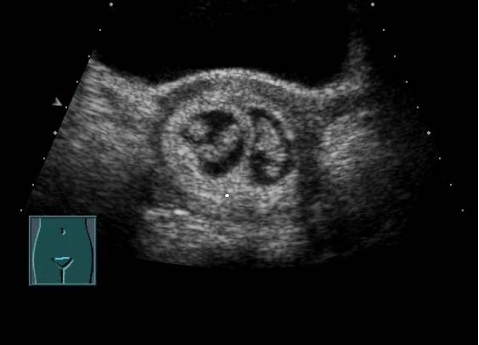

单 胎 双 胎

第二次就是在我们怀孕11~13+6周的时候的NT超声检查

这次检查我们可以了解到NT的厚度、胎儿头臀长、静脉导管及鼻骨的相关信息。不对胎儿结构进行评价。如果发现NT增厚的胎儿、产科医生根据孕妇的自身情况,建议孕妇进行下一步检查(无创DNA 或是羊水穿刺,排除染色体的问题)。

NT正常范围的孩子 NT增厚的孩子